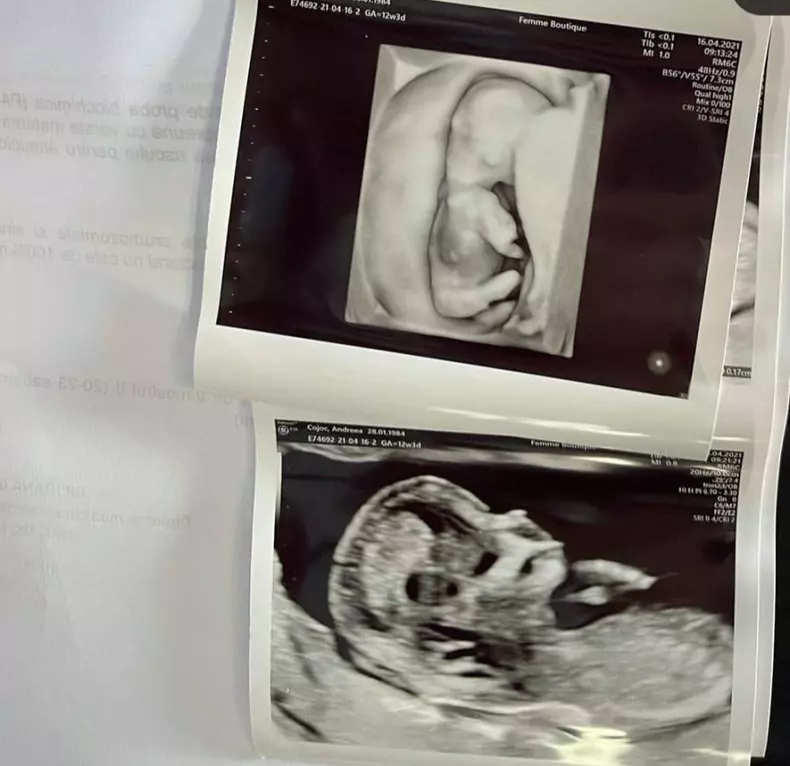

Andreea Popescu, fosta dansatoare a Deliei, e gravidă a doua oară. Primele imagini de la ecograf